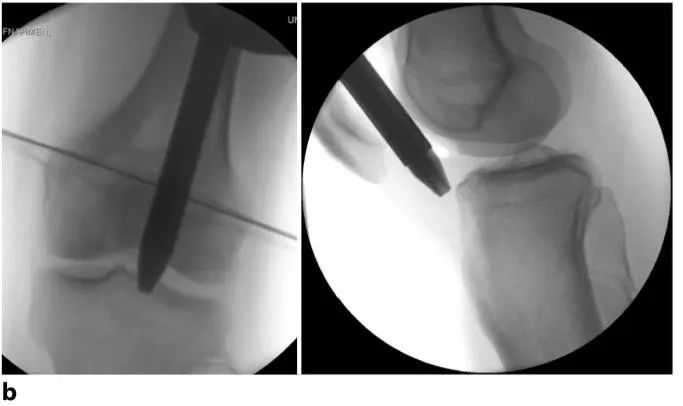

Gambar 8a The assembly cecekelan diselapkeun underneath patella ngaliwatan gabungan patellofemoral arah titik Éntri nu dipikahoyong dina tibia nu (Gambar 9). Dina kalolobaan kasus, patella bakal gerak rada medially atanapi laterally salila panempatan instrumen. Alur dina gabungan patellofemoral biasana nungtun jarum trocar ka posisi anu leres sacara otomatis.

Gbr. 8b Posisi dikonfirmasi dina duanana planes ngagunakeun fluoroscopy sarta dilereskeun mana perlu. Jarum trocar lajeng diganti ku guidewire porous, a guidewire nu ngaliwatan liang tengah guidewire jeung ujung nu diselapkeun kana metaphysis tibial proksimal pikeun mastikeun posisi bener.

Gambar 8c Nalika guidewire dina posisi suboptimal, a guidewire kadua bisa dipaké pikeun nyieun slight pangaluyuan dina posisi hadé ngaliwatan guidewire porous, nepi ka maksimum 4,3 mm Minangka alternatif, meureun nya gampang mimitian ku guidewire jeung nempatkeun eta tanpa bantuan dina titik optimal asupna. Instrumén sisipan jeung guidewire lajeng slid ngaliwatan guidewire.

Gbr. 9a Muka rohangan medullary tina titik asupna idéal nyaéta léngkah kritis dina prosedur bedah. Dina pesawat anteroposterior, ieu aspék medial tina spur tibial gurat. Dina pesawat gurat, titik éntri anu leres aya dina transisi antara permukaan artikular sareng korteks anterior.

Gbr. 9b Posisi bener tina guidewire nyaeta dina garis kalawan sumbu tibial dina pesawat anteroposterior sarta sacaket paralel ka cortex anterior sabisa dina proyéksi gurat. Guidewire condong mindahkeun posteriorly.

Gambar 9c Dina kasus dimana pin atanapi paku teu tiasa diselapkeun leres, blocking paku atawa pin mantuan pikeun pituduh paku kana posisi nu bener.